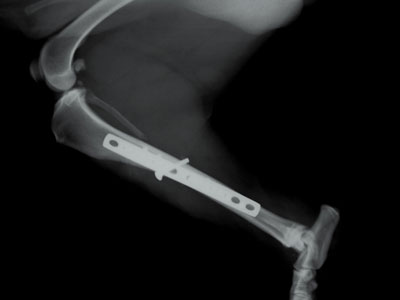

Μεσαίου μεγέθους 1-2 ετών με λοξό τέλειο κάταγμα στο άνω / 3 της διάφυσης της αριστερής κνήμης. Πραγματοποιήθηκε χειρουργική επέμβαση στις 01/10/09. Τοποθετήθηκε μεταλλική πλάκα στην έσω επιφάνεια της κνήμης με 6 κοχλίες και συμπιεστικός κοχλίας εγκάρσια στην καταγματική γραμμή. Το ζώο βρίσκεται υπό περιορισμό.Η αποκατάσταση ήταν 100 % και τα υλικά αφαιρέθηκαν 7 μήνες μετά .